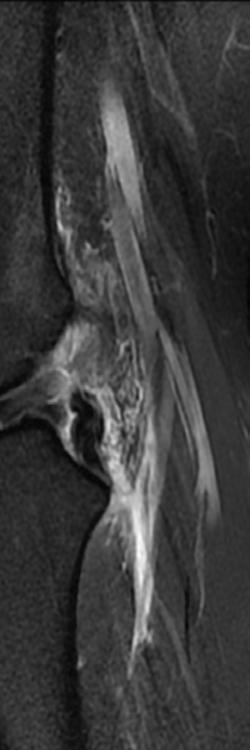

Der Blick ins Knie

Wenn es bei Bewegung schmerzt oder zwickt, ist eine exakte Diagnose entscheidend. Da kommen auch die Radiologen ins Spiel: PD Dr. Thorsten Klink, Direktor des Instituts für diagnostische und interventionelle Radiologie an der Klinikum Bayreuth GmbH, macht einen Blick ins Knie möglich. Hier wird deutlich, was moderne Bildgebung kann. KREUZBANDRISS

KLINIKUM BAYREUTH GMBH > RADIOLOGIE O B E R S C H E N K E LK N O C H E N S C H I E N B E I NK N O C H E N GELENKERGUSS K N I E S C H E I B E K N I E S C H E I B E Kreuzband-

VORDERES KR E U Z B A N D HINTERES KREUZBAND

Riss Normales Kreuzband

KreuzbandPlastik

35 S C H I E N B E I NK N O C H E N S C H I E N B E I NK N O C H E N O B E R S C H E N K E LK N O C H E N O B E R S C H E N K E LK N O C H E N K N I E S C H E I B E S C H RAU B E KREUZBANDPLASTIK

H I N TERES KREUZB A N D